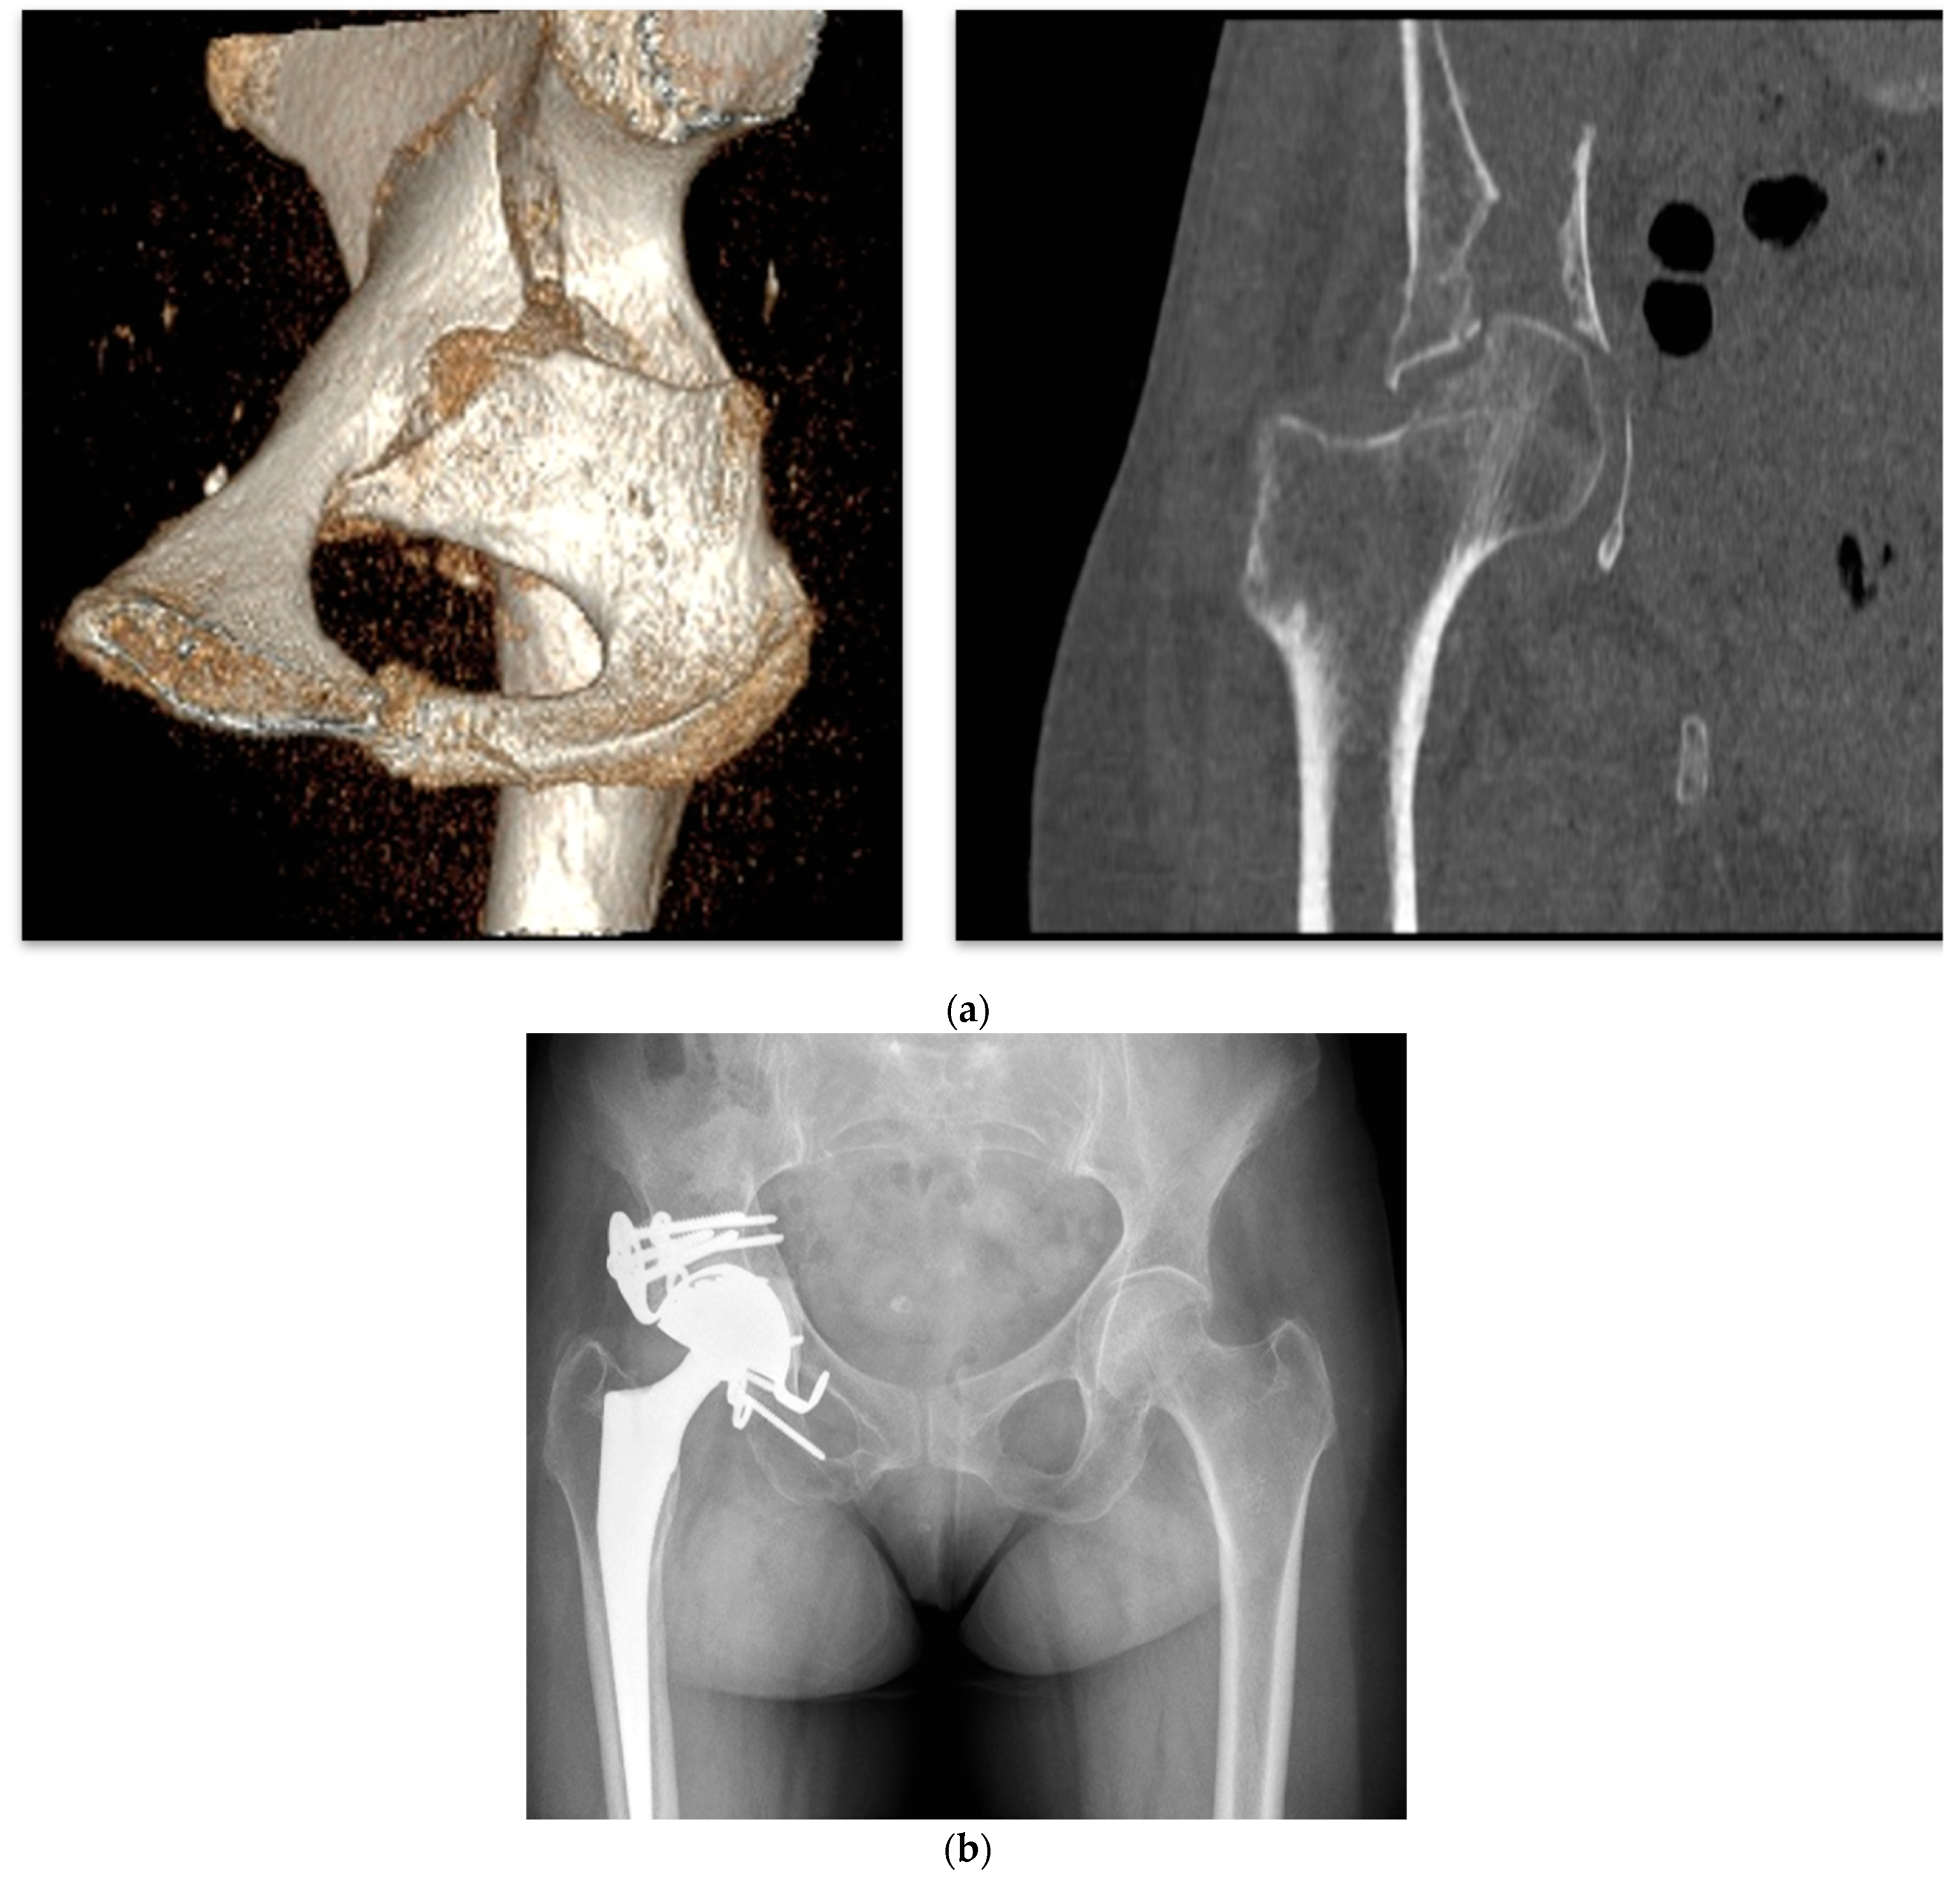

4.1. Delayed THA, Neglected, or Conservatively Treated Acetabular Fractures

Acetabular Exposure, Preparation, and Cup Fixation

4.3. Acute THA in Acetabular Fractures